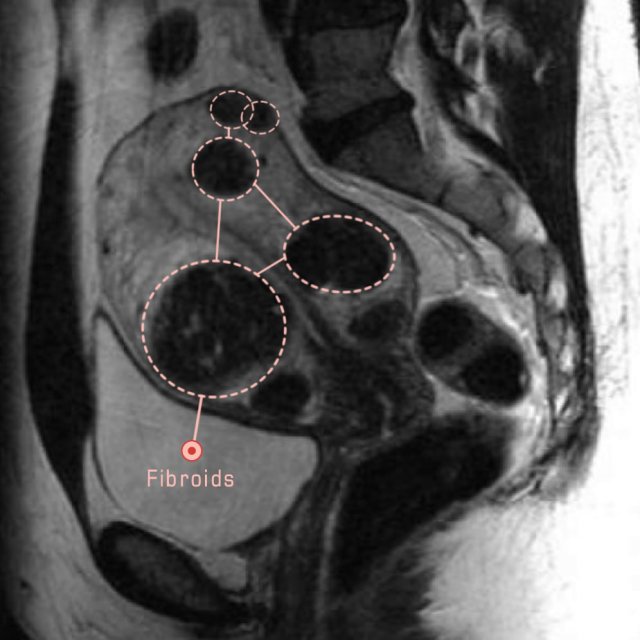

Pelvic MRI for Fibroids – Why You Need an MRI to Detect Fibroids

Detecting fibroids with imaging – medical empowerment

Fibroids UFE | Body MRI